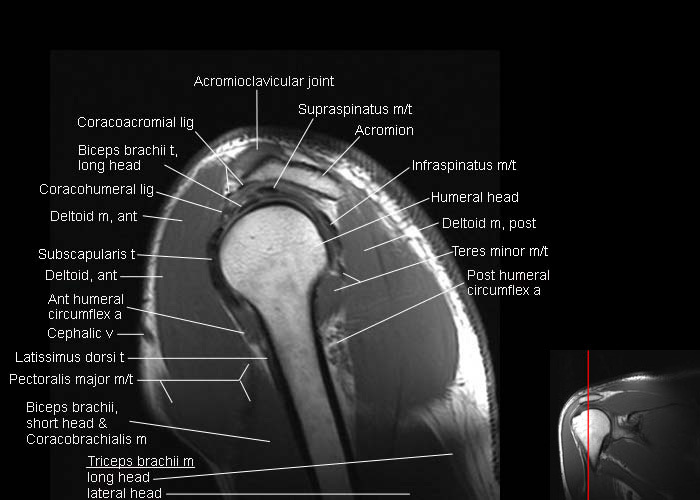

shoulder anatomy

sagittal